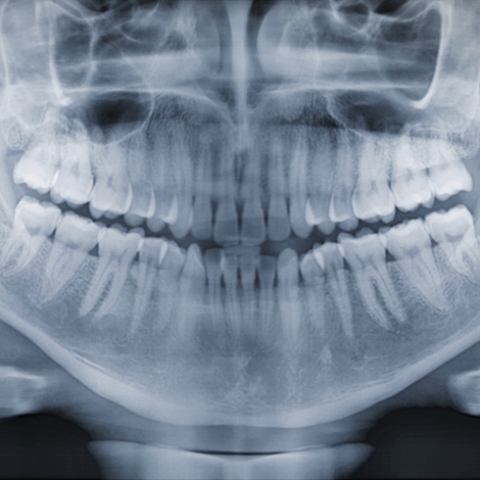

Herudover tages i nogle tilfælde Panorama-røntgen, som er et stort røntgenbillede der giver et overblik over hele tandsættet og ansigtets anatomiske strukturer.

Billedet bruges især til behandlingsplanlægning og vurdering af knogle/nerver/kæbehulens placering, når indgreb i relation til disse strukturer er nødvendig.